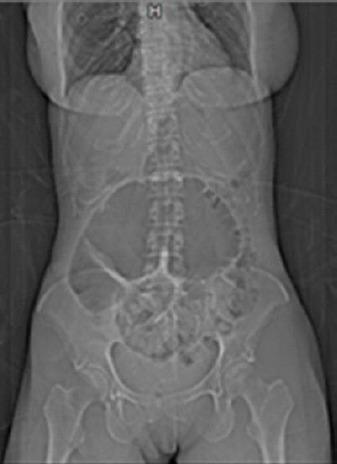

Caecum volvulus (CV) is defined as an axial twisting that causes an inversion position of the caecum, ascending colon and terminal ileum. This anatomical finding is responsible for some clinical features. Obstruction and strangulation are the most important and life-threatening.

We are presenting a 50 years old woman presented to the hospital with sudden acute severe abdominal pain and distension of about 24 hours associated with vomiting and no flatus.

盲肠扭转(CV)被定义为一种导致盲肠、升结肠和回肠末端发生倒转位置的轴向扭转。这一解剖学发现导致了一些临床特征。梗阻和绞窄是最重要且危及生命的。

我们报告一名50岁女性,因突发急性剧烈腹痛和腹胀约24小时入院,伴有呕吐且无排气。